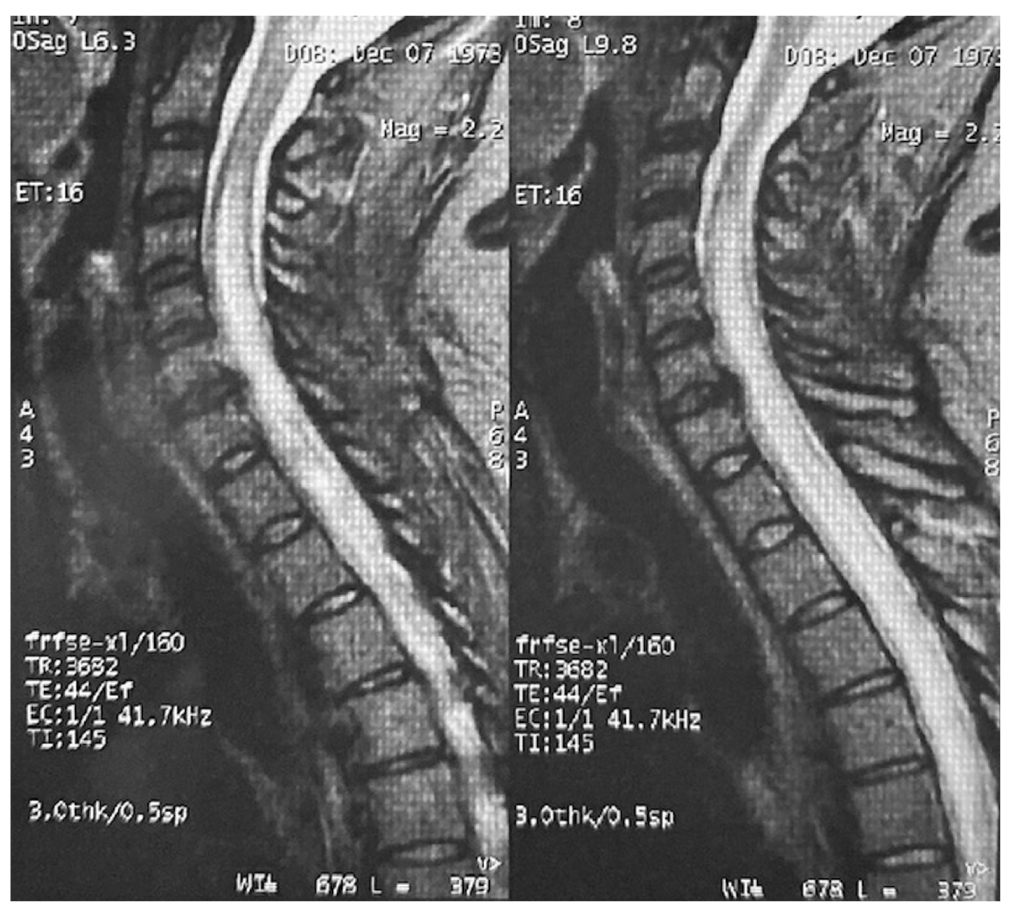

Нейровизуализационные изменения спинного мозга свидетельствуют о демиелинизирующем поражении более 3 шейных сегментов по типу продольно-распространенного поперечного миелита, что согласуется с данными клинической картины (рис. 1).

Рис. 1. МР-картина демиелинизирующего заболевания спинного мозга c повышенным патологическим МР-сигналом на уровне краниовертебрального перехода и на уровнях С3-Th12 позвонков (на всем протяжении спинного мозга). / Fig. 1. MR-picture of a demyelinating spinal cord disease with an increased pathological MR signal at the level of the craniovertebral junction and at the levels of C3-Th12 vertebrae (throughout the spinal cord).